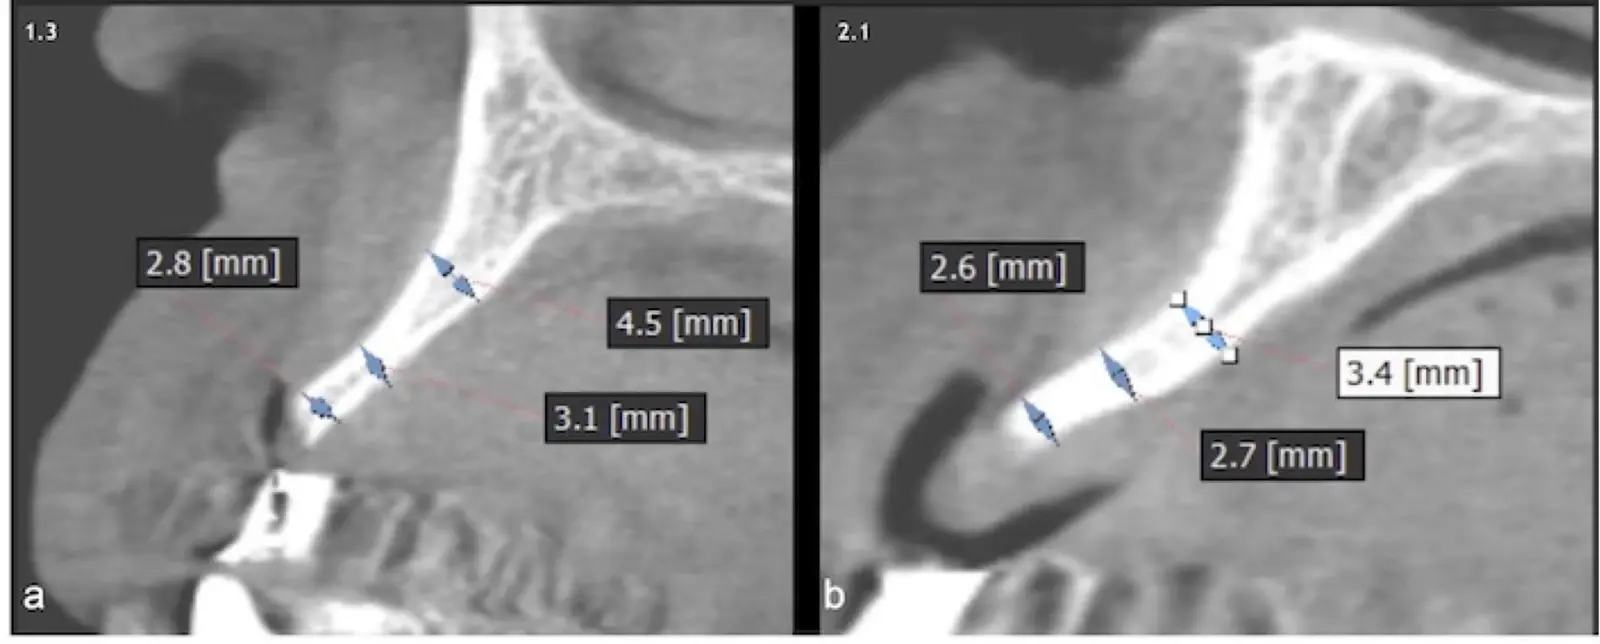

Paciente de sexo femenino de 53 años llega a la consulta solicitando una prótesis implantosoportada. En la evaluación clínica se observa un edentulismo total superior con una severa reabsorción ósea generalizada, a excepción de la pieza 2.3, que se encontraba en estado de remanente radicular. En la evaluación tomográfica se corrobora el hallazgo clínico y se indica una reconstrucción de reborde con injertos en bloque previo a la planificación de implantes dentales.

Figura 19. Tomografía computarizada de la zona receptora. Pieza 1.3 (a). Pieza 2.1 (b).